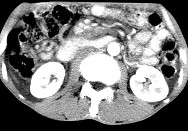

单项选择题女,50岁, 中上腹疼痛,消瘦乏力, 影像检查如下图,最佳的诊断为( )

A、胰岛素瘤

B、慢性胰腺炎

C、急性胰腺炎

D、腹膜后淋巴瘤

E、胰腺癌并腹膜后淋巴结转移